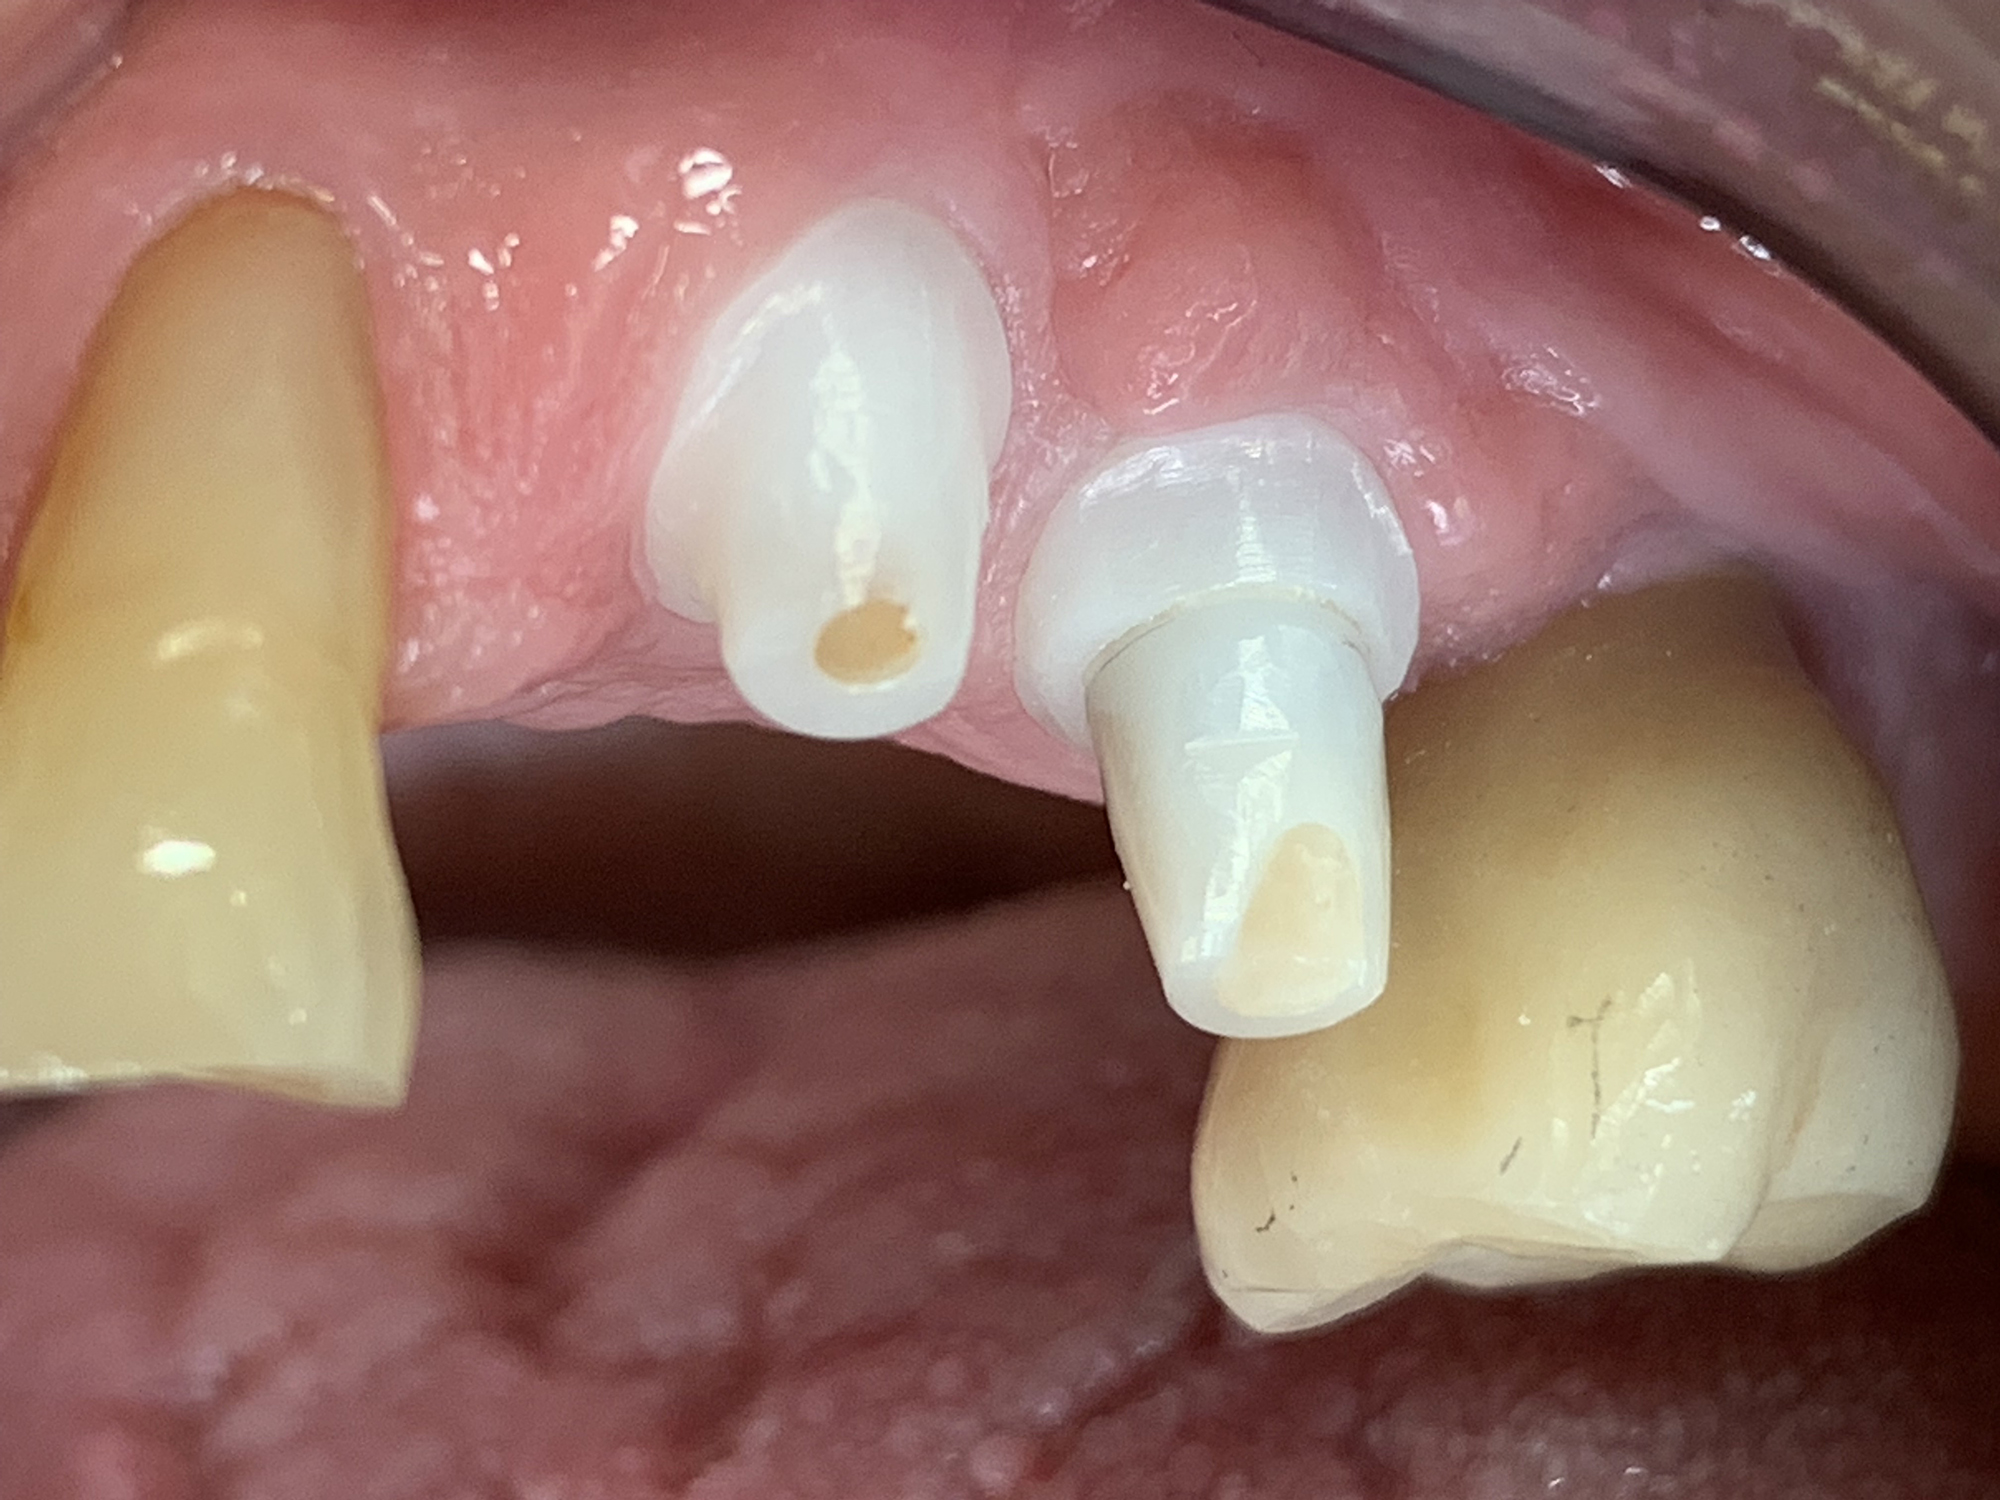

Keramikimplantate

Wir setzen auf hochwertige Keramikimplantate von Swiss Dental Solutions. Diese sind metallfrei, ästhetisch, verträglich und lassen sich oft in nur einer Sitzung einsetzen – für ein natürlich schönes Lächeln.

Keramikimplantat freigestellt

Vorteile Keramik Implantate

• Weiß

• metallfrei

• immunologisch neutral

• biokompatibel

• hochästhetisch

• keine Periimplantitis

• keine freien Elektronen an der Oberfläche – keine Reaktion mit Gewebe

• kein Störfeldcharakter

• kurze Behandlungsdauer